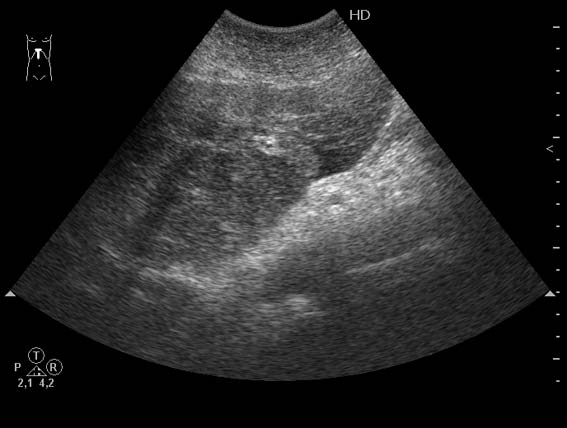

Женщина 82 лет с болями в эпигастральной области.

Очаги были пропущены при ультразвуковом исследовании.

Потому что при повторном УЗ-исследовании (уже после КТ) они были обнаружены.Serg писал(а):Почему Вы пишете, что очаги пропущены?

The accuracy of unenhanced US in the assessment of hepatic metastases is lower than that of contrastenhanced CT and MR. In series with a true gold standard, its sensitivity ranges between 50% and 76% (Table 18.2) (Clarke et al. 1989; Ohlsson et al. 1993; Wernecke et al. 1991). Problems encountered with US are its operator-dependent nature (making it difficult to use for follow-up staging), the sometimes difficult access to subdiaphragmatic areas of segments IVa and VIII and poor liver-to-lesion contrast of isoechoic lesions, especially in small metastases. For lesions smaller than 1 cm, the false-negative rate is as high as 80% (Wernecke et al. 1991). The false-positive rate of US is in the order of 5–10% on a by patient basis and considerably higher on a by lesion basis.